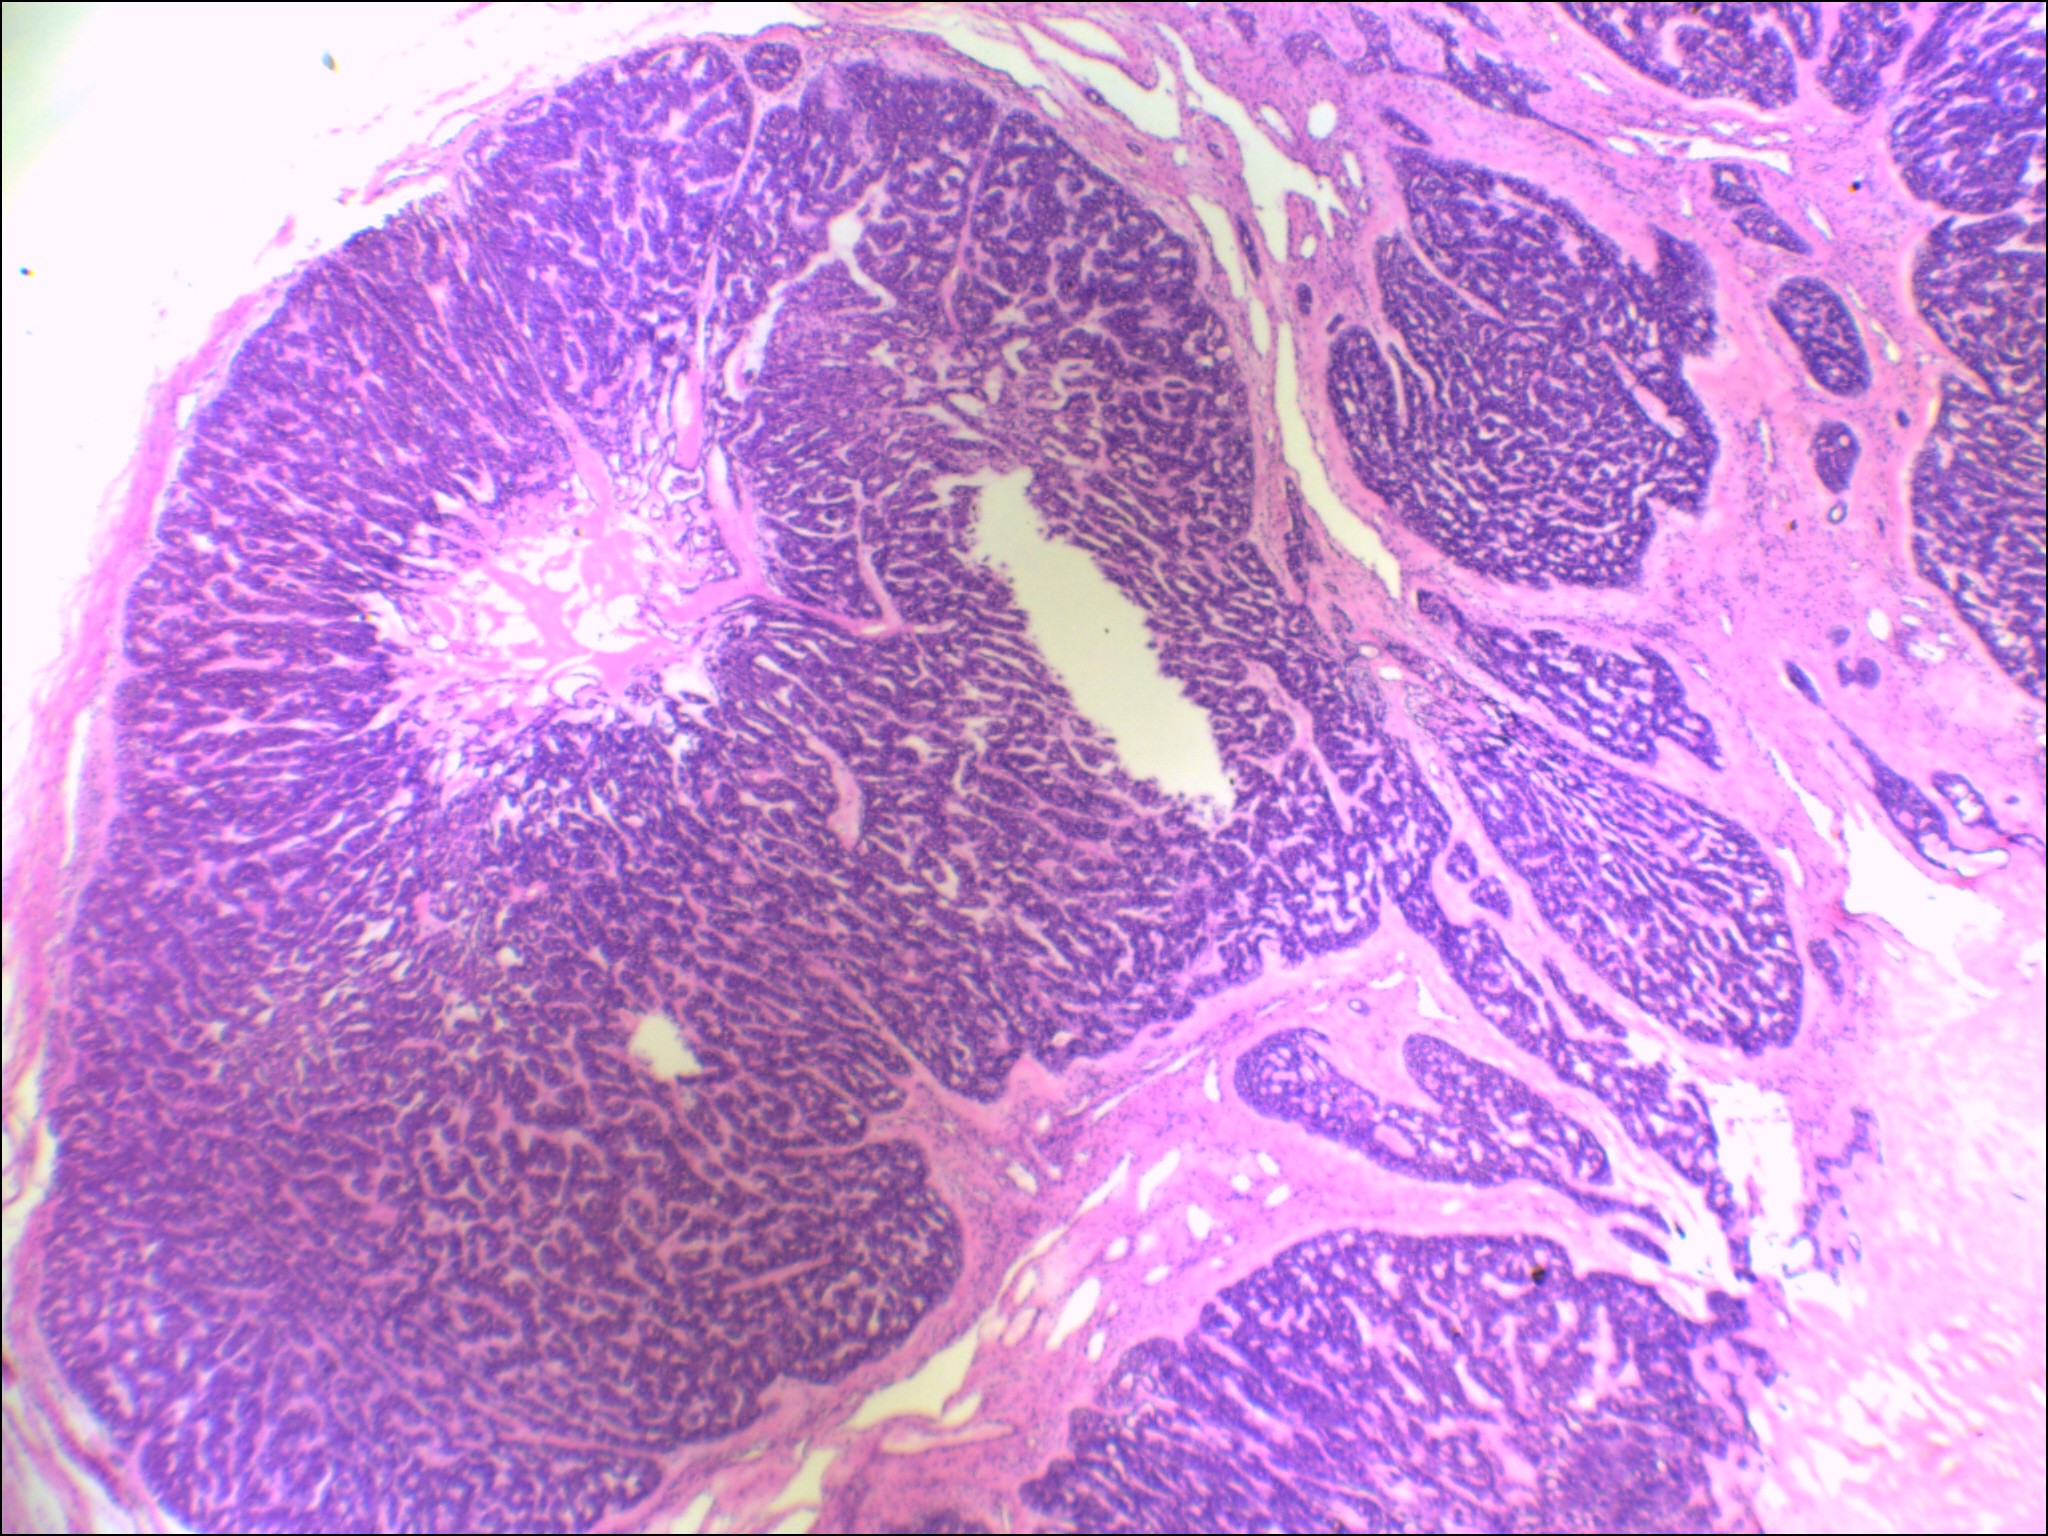

左侧腮腺肿物

性别

女

年龄

48岁

发现颈部肿块20余年

肿块大小:4×3×2.8cm,表面光滑,有包膜,切面灰白色,质硬。

图3

首先考虑基底细胞腺瘤。